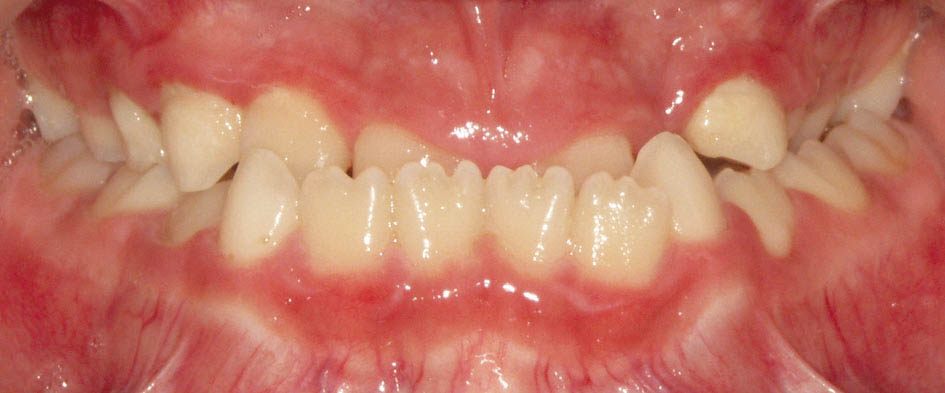

در این مواقع بیمار برای رسیدن به حداکثر تماس بین دندانی (CO) مندیبل را جلو میآورد تا خلفیها به یکدیگر تماس پیدا کنند (انحراف قدامی مندیبل) و شما یک کراس قدامی (شکل 24-5) و ایجاد یک رابطه کلاسIII مولری را میبینید.

وقتی انسیزورهای بالا پروترود شوند چون تماس پیشرس برطرف میشود، دیگر انسیزورهای پائین در زمان اکلوژن CR به آنها تماس نخواهند داشت و در همان CR به حداکثر تماس میرسند. پس دیگر نیازی به جلو آمدن مندیبل برای رسیدن به حداکثر تماس دندانی نیست، لذا رابطه کلاسIII مولری کودک اصلاح میشود.

اگر انحراف قدامی مندیبل باشد با درمان کراس دندانهای قدامی، انحراف قدامی مندیبل از بین میرود و مندیبل عقبتر قرار میگیرد. اکلوژن اولیه که به همراه انحراف است یک اکلوژن کاذب است. اگر کلاسIII باشد یک کلاسIII کاذب است که بعد از درمان، مندیبل عقب رفته و کلاسI میشود. اگر کلاسI باشد به آن کلاسI کاذب میگوییم و با اصلاح انحراف مندیبل، بیمار کلاسII میشود و اگر کلاسII بوده به آن کلاسII کاذب میگوییم و با اصلاح انحراف مندیبل، میزان کلاسII او تشدید میشود.

از طرفی با پالاتالی شدن انسیزورهای بالا و تماس با دندانهای پایین شاهد سایش مینای دندانهای درون کراس میباشیم.

پس بنا به دلایل زیر درمان دندانهای درون کراس قدامی میبایستی سریعاً انجام شود:

1. انحراف قدامی مندیبل

2. تحلیل لثه دندانهای قوس پایین

3. سایش مینای دندان